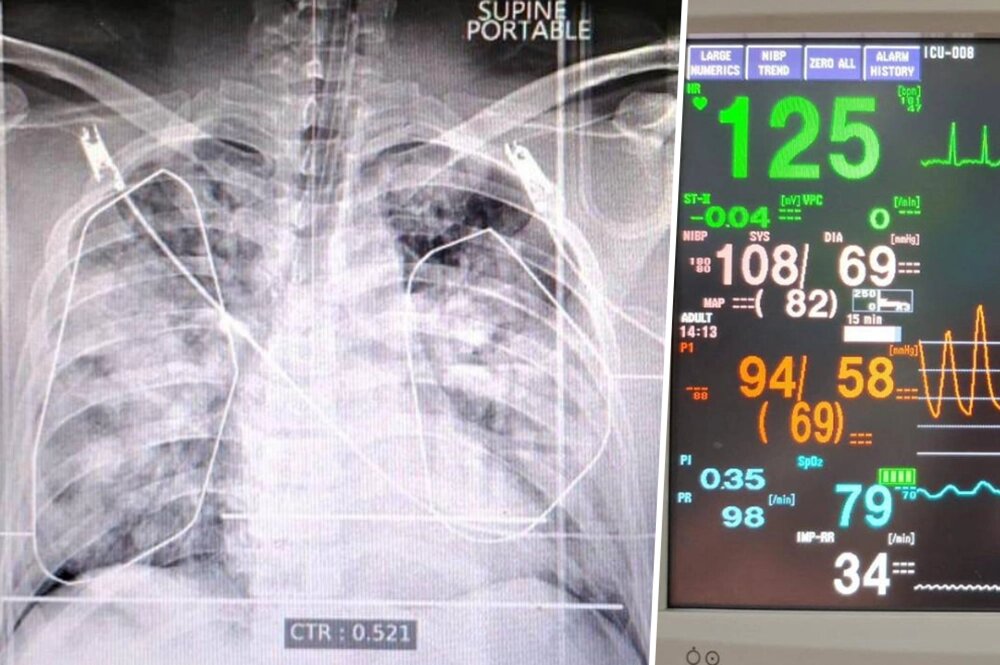

Рентгент-снимок и жизненные показатели Паши Техника. Фото: соцсети